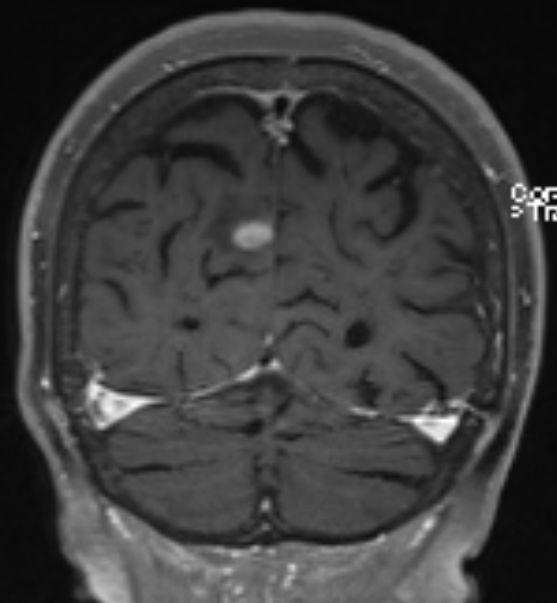

84-jährige Frau, die vor 3 1/2 Jahren einen 35 mm großen derben

Rektumpolypen entwickelte. Die submuköse Exzision ergab ein malignes Melanom

mit Infiltration der tiefen Muskulatur und Ummauerung größerer Gefäße. BRAF+.

Vor 2 Jahren Rektumschleimhau-Rezidiv und Metastase rechts pararektal:

anteriore Rektumresektion. Vor 4 Monaten Lungenmetastase und singuläre

Hirnmetastase re occipital. Dabrafinib + Trametinib nach 2 Zyklen wegen

Hepatotoxizität und Hautausschlag abgebrochen. Jetzt: RT der Hirnmetastase

und des pararektalen Tumors.  |